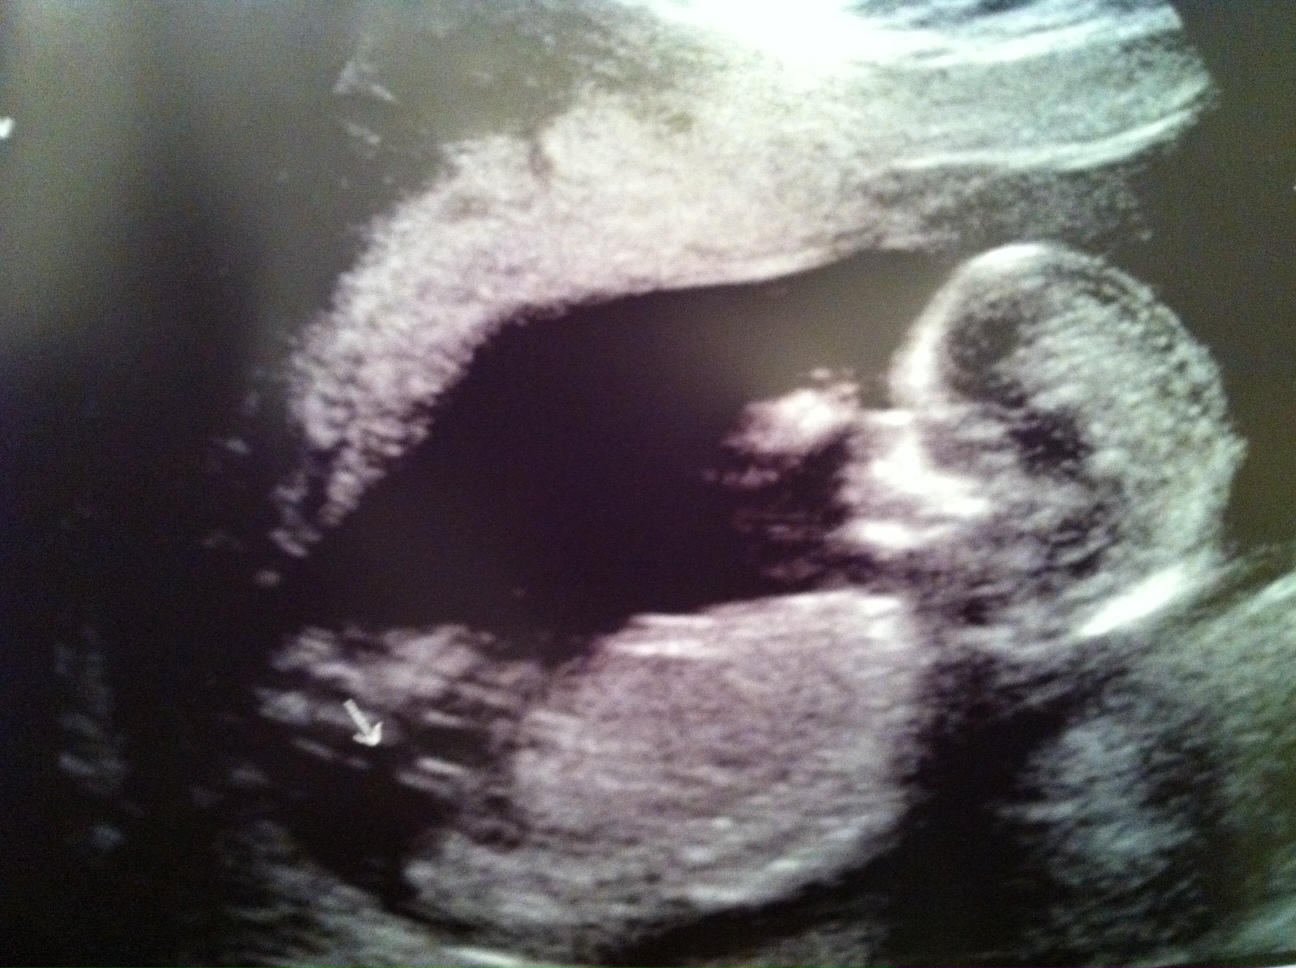

Sorry the pic is so huge. There's an arrow pointing at the nub.

VERY girly! Spine is curved....but that's one hellavu fork.

it doesn't look boy to me... again 13 weeks is really early so im not saying its not a boy. it is a deep fork but im not seeing anything that screams boy. a potty shot would be useless right now, they aren't accurate until 15 weeks and those nubs both look the same in potty shots until then.

not saying it is a girl but im not convinced its a boy. baby's spine is bent so its hard to tell if that nub is actually parallel with the spine. also its got a fork, usually girls have a deep fork like that and 3rd, because a 13 week potty shot is unrealiable. it means nothing. if i showed you a girl and a boy potty shot at 13 weeks you probably coudln't tell the difference.

Only you know what you saw during your scan but I have to agree with several others that this is NOT a convincing boy nub shot. The spine is curved as many have said. I'm not great at guessing these, I feel like many are ambiguous, but this is certainly not a "definitely" boy OR girl shot IMHO. There's still hope ... I know sometimes that just makes it harder though, but I wouldn't give up on your dream yet :fingers:

I agree with lobella, my first thought was boy because it looks so angled, but when you look at the spine the nub is parallel to the end of the spine, plus it is so forked. So I think you know as much as before the scan!